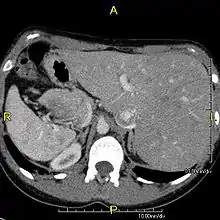

Axial CT image showing situs inversus (liver and IVC on the left, spleen and aorta on the right) in a patient with Kartagener syndrome.

The condition affects all major structures within the thorax and abdomen. Generally, the organs are simply transposed through the sagittal plane. The heart is located on the right side of the thorax, the stomach and spleen on the right side of the abdomen and the liver and gall bladder on the left side. The heart's normal right atrium occurs on the left, and the left atrium is on the right. The lung anatomy is reversed and the left lung has three lobes while the right lung has two lobes. The intestines and other internal structures are also reversed from the normal, and the blood vessels, nerves, and lymphatics are also transposed.